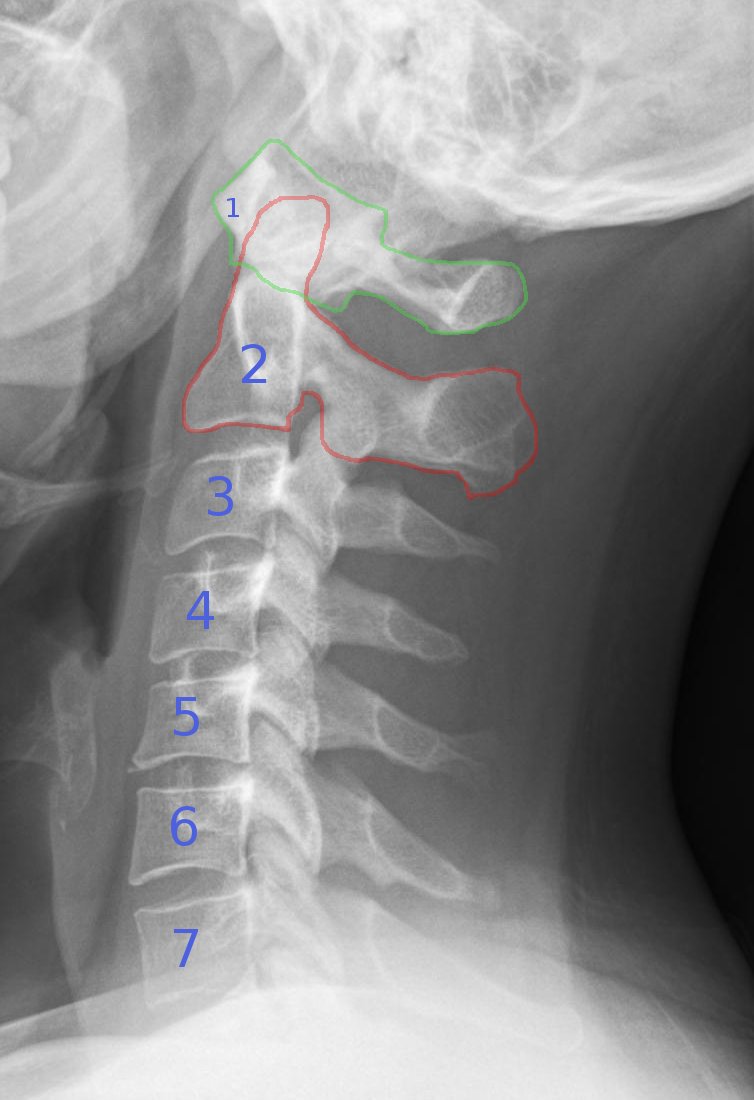

경추(cervical vertebrae)

두개골 아래에서 시작해 척주 아래로 진행되는 7개의 추골(C1-C7)

경추의 엑스레이 이미지(X-ray of cervical vertebrae)